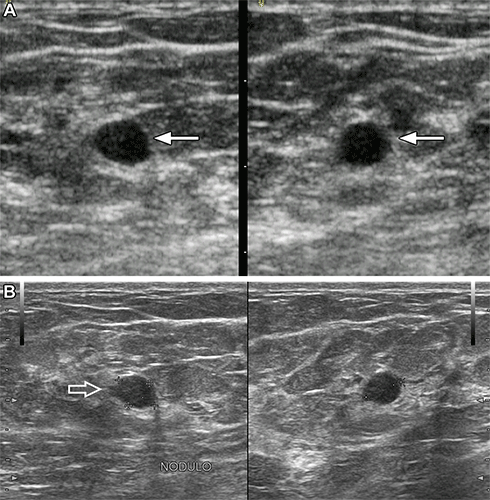

Images in a 37-year-old woman show a palpable mass due to low-grade ductal carcinoma in situ. (A) Orthogonal portable US images show a hypoechoic oval mass with subtly indistinct margins (arrows), assessed as probably benign by artificial intelligence (AI). (B) Orthogonal standard-of-care US images show focal microlobulation (arrow) and were assessed as suspicious with AI and as Breast Imaging Reporting and Data System 4A by the radiologist. US-guided core biopsy and excision showed estrogen and progesterone receptor positive low-grade ductal carcinoma in situ.